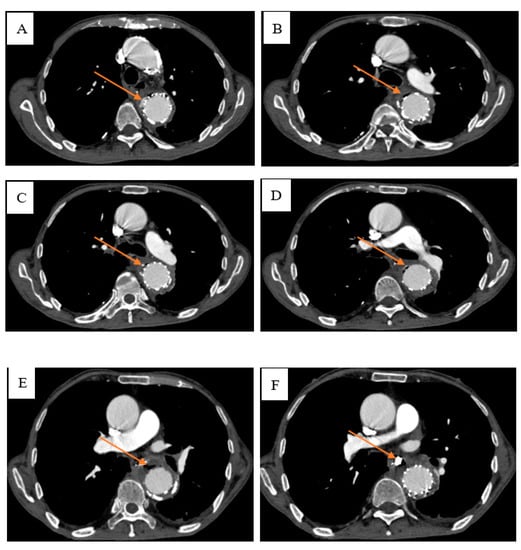

Aorticoesophagal Fistula Combined with Upper Gastrointestinal Bleeding after Endovascular Dissection of Thoracic Aortic Aneurysm